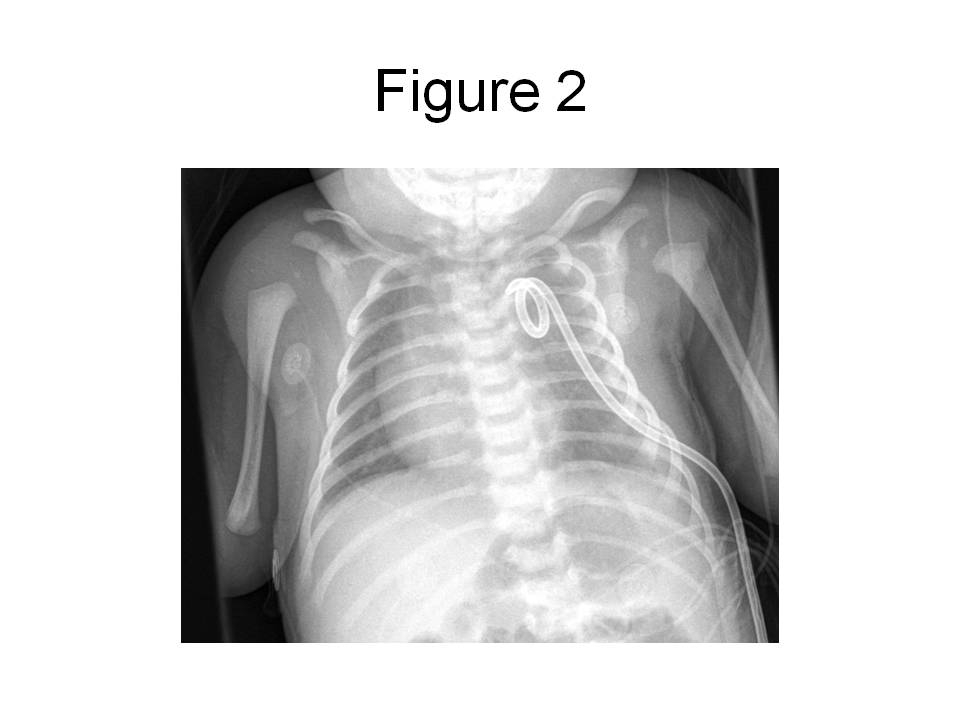

In the ER, a peripheral intravenous catheter was placed and empiric ampicillin and cefotaxime given.  The child was transferred to the pediatric intensive care unit (PICU).  In the PICU, the child was intubated for respiratory distress and a percutaneous tube thoracostomy was performed on the left side.  The pleural fluid was grossly cloudy with a triglyceride level of 1075 mg/dL and 32,000 WBC/mm3 which were predominantly (90%) lymphocytes.  The protein content of the fluid was 2.9 g/dL and the LDH was 307 U/L.  Gram’s stain of the fluid revealed 2+ WBC and the cultures remained negative for 72 hours, at which point antibiotics were discontinued.  The child’s chest radiograph after tube placement revealed resolution of the effusion with no evidence of intrapulmonary masses (see figure 2) and the child was subsequently extubated.

Figure 2. Portable (AP) chest radiograph obtained in the PICU after chest tube placement and extubation reveals complete resolution of the pleural effusion.